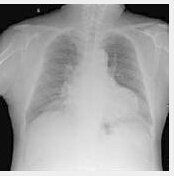

(一)呼吸系統:早期可見呼吸頻率(RR)加快>20次/分,吸空氣時動脈氧分壓(PaO2)下降≦70mmHg,動脈氧分壓與吸入氧濃度之比(PaO2/FiO2)>300。X線胸片可正常。中期RR>28次/分,PaO2≦60mmHg,動脈二氧化碳氧分壓(PaCO2)<35mmHg ,PaO2/FiO2<300。胸片可見肺泡實性改變(≦1/2肺野)。晚期則呼吸窘迫,RR>28次/分,PaO2≦50mmHg,PaCO2>45mmHg,PaO2/FiO2<200 。胸片肺泡實性改變加重(≧1/2肺野)。

肺臟 急性肺損傷 急性呼吸窘迫綜合徵

PaO2/FiO2≤300mmHg PaO2/FiO2≤200mmHg